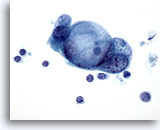

画像 4

肝FNA – 良性肝細胞

反応性変化を来した肝細胞。核は大小不同で、二核を有しています。

40倍

画像 4

肝FNA – 良性肝細胞

反応性変化を来した肝細胞。核は大小不同で、二核を有しています。

40倍